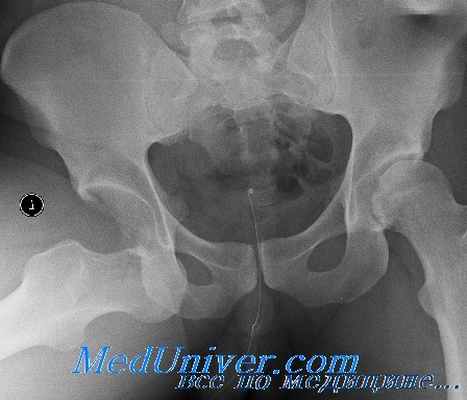

Тазовые переломы следует исключать при боли в области таза или бедра, или при массивной травме. Рентгенография области таза в передне-задней проекции позволяет выявить большинство переломов.

Перелом со смещением означает, что нарушается целостность тазового кольца, и можно заподозрить другой перелом или поражение синдесмоза или связочного аппарата. Могут быть необходимы рентгеновские исследования в специализированных проекциях (например, рентгенограмма в косой проекции по Жюде позволяет визуализировать вертлужную впадину).